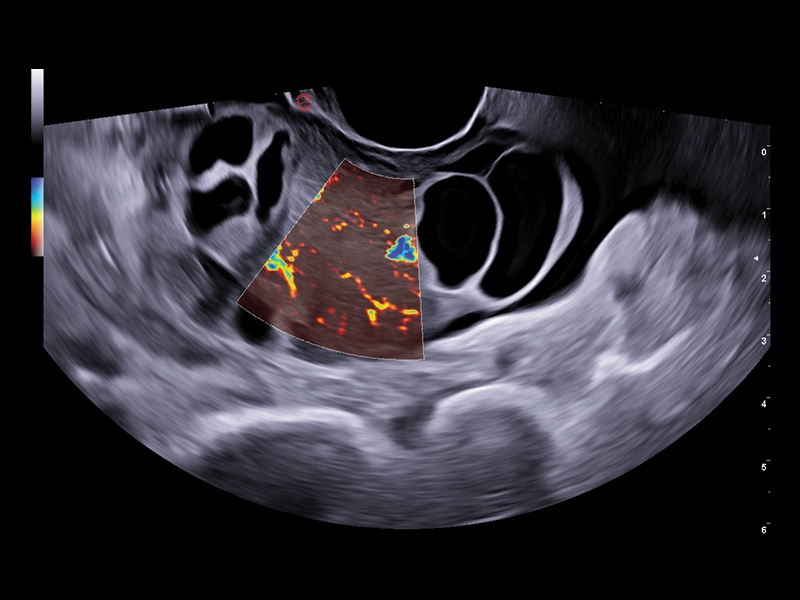

MyLab™E80 - Power Doppler - Gynaecology

MyLab™E80 - Power Doppler - Gynaecology